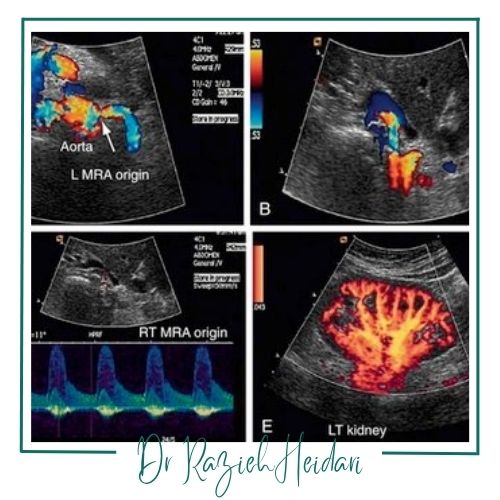

سونوگرافی داپلر عروق

این روش یک روش تصویربرداری پیشرفته است که برای بررسی جریان خون در عروق سطحی و عمقی بدن استفاده میشود و با استفاده از امواج صوتی جریان خون را در رگها بهصورت رنگی نمایش میدهدکه به پزشک کمک میکند تا مشکلاتی مانند انسداد عروق، گرفتگی شریانها و وجود لختههای خون را شناسایی کند.

این روش در تشخیص مشکلات عروقی مانند ترومبوز وریدی عمقی (DVT)، نارسایی وریدی و بیماریهای شریانی مثل آترواسکلروز مؤثر است و برای بیمارانی که مشکلات گردش خون دارند یا بعد از جراحیهای عروقی استفاده میشود. این روش به پزشکان کمک میکند تا درمانهای مناسب برای بهبود جریان خون و پیشگیری از عوارض جدیتر را تعیین کنند.

ارزیابی کلیهها: برای بررسی جریان خون در کلیهها بهویژه در بیمارانی با فشار خون بالا، بیماریهای مزمن کلیوی یا مشکوک به تنگی شریان کلیوی.